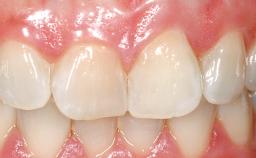

Late Flapless Placement of an Implant in a Maxillary Left Central Incisor Site

A 39-year-old male patient presented with a chief complaint of discomfort and gingival discoloration around his maxillary left central incisor. He was in good general health and was a non-smoker. His past dental history was significant because of the traumatic fracture of tooth 21 in a sporting accident at age 13. Initial dental treatment included endodontic therapy and a full-coverage restoration. The patient became symptomatic 5 years later, when structural failure of the tooth resulted in the dislodgment of the crown. Endodontic retreatment, apical surgery, and post-and-core restoration were performed.

Soft Tissue Contour and Volume Slightly compromised